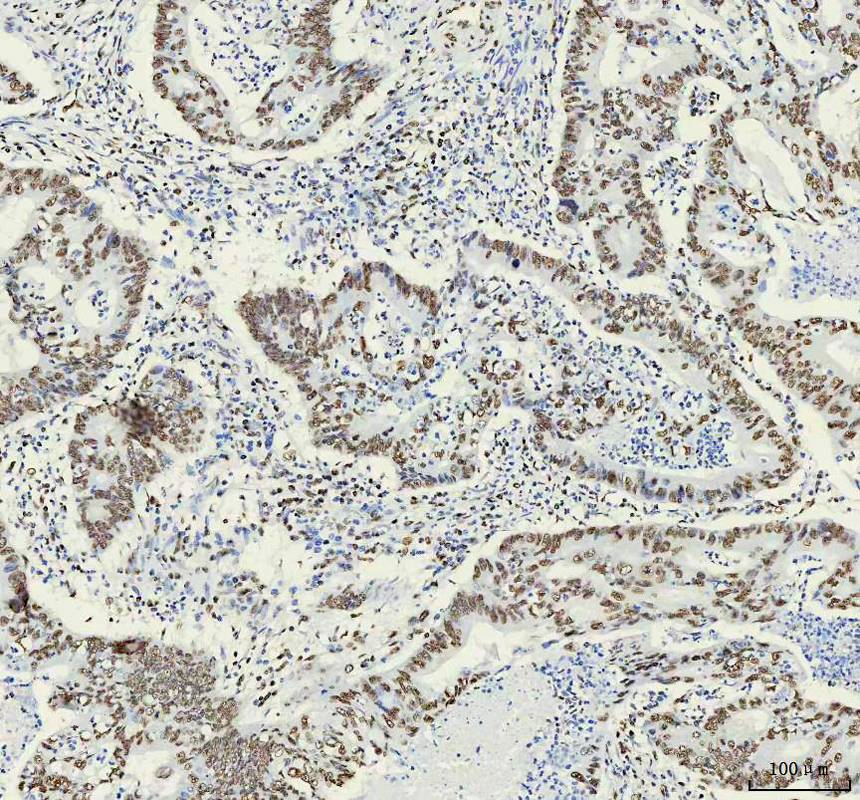

IHC analysis of HNRNPM using anti-HNRNPM antibody (M06017-1) .

HNRNPM was detected in a paraffin-embedded section of human stomach cancer tissue. The tissue section was incubated with rabbit anti-HNRNPM Antibody (M06017-1) at a dilution of 1:200 and developed using HRP Conjugated Rabbit IgG Super Vision Assay Kit (Catalog # SV0002) with DAB (Catalog # AR1027) as the chromogen.